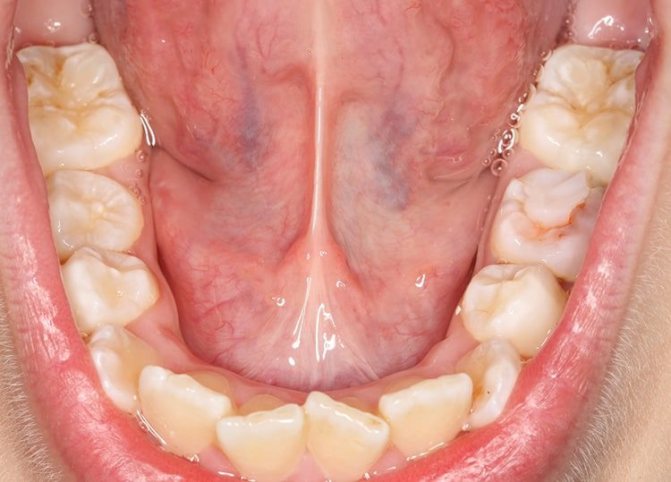

При внешнем осмотре асимметрии лица нет. Лишь в тех случаях, когда киста прорастает в под подбородочную область (раздвигает волокна челюстно — подъязычной мышцы) можно увидеть припухлость в данном участке. Открывание рта свободное. В подъязычной области имеется полушаровидное выпячивание округлой или овальной формы, плотно- или мягко-эластичной консистенции, безболезненное (рис. 23.6.1 — 23.6.3). Слизистая оболочка над выпячиванием растянута и истончена, полупрозрачна с голубоватым оттенком. Пунктировать кисту нельзя, т.к. после пункции она опорожняется (выделяется прозрачная, слизистая, тягучая желтоватая жидкость). Киста находится рядом с протоком поднижнечелюстной железы, но не передавливает его. В этом можно убедиться, проводя зондирование протока (введение полиэтиленового катетера) или сделав сиалографию поднижнечелюстной железы

Рис. 23.6.1.

Вид больного с ранулой, расположен-ной в переднем отделе подъязычной области.